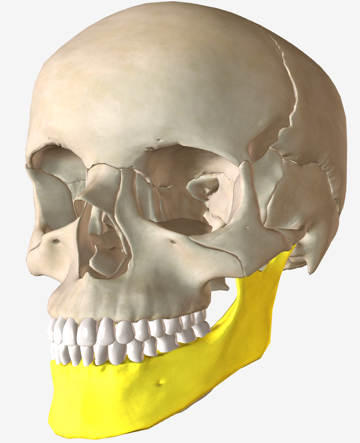

CBCT-based image analysis plays a significant role in diagnosing a disease or deformity, characterizing its severity, planning the treatment options, and estimating the risk of potential interventions. The core image analysis framework involves the detection and measurement of deformities, which requires precise segmentation of CMF bones. Landmarks, which identify anatomically distinct locations on the surface of the segmented bones, are placed and measurements are performed to determine the severity of the deformity compared to traditional 2D norms as well as to assist in treatment and surgical planning. Figure 1 shows nine anatomical landmarks defined on the mandible.